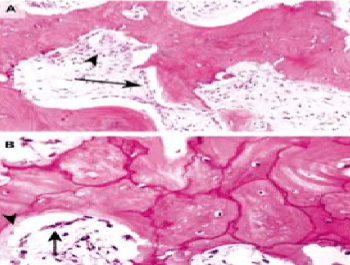

Osteolytic: ↑ osteoclast activity – abnormally large osteoclasts with many nuclei

Numerous resorption pits

Mixed osteoblastic-osteoclastic stage: Prominent osteoblasts → new bone woven or lamellar which is eventually remodeled to lamellar bone

Osteosclerotic stage: Osteoblastic & osteoclastic activity cease → thickened trabeculae which lack structural stability → fractures easily

Paget’s disease of bone Morphology

Mosaic pattern of dense lamellar bone in sclerotic phase

Prominent irregular cement lines & haphazard orientation of lamellar bone

Sclerotic phase: bones are thicker than normal but structurally unstable & fracture easily